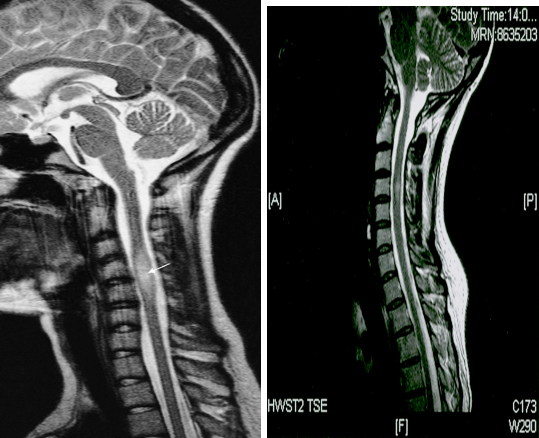

Typical findings on MRI

- Multiple sclerotic plaques (most commonly found in the periventricular white matter) with finger-like radial extensions (Dawson fingers) related to demyelination and reactive gliosis

- In T1: hypointense or isointense lesions

- In T2 and FLAIR: hyperintense lesions, typically round or oval in shape and found in both hemispheres

- Contrast-enhancement of active lesions

(a)Axial FLAIR sequence at the level of the lateral ventricles shows periventricular areas of linear and ovoid hyperintense signal orientated perpendicular to the body of the right lateral ventricle. This feature is known as Dawson fingers and is strongly associated with multiple sclerosis. It represents perivascular inflammation around the subependymal veins.

(b)Parasagittal T2-weighted MRI shows plaques of demyelination as high signal in the white matter, particularly along the margins of the lateral ventricles and immediately next to cortical grey matter.

(c)Post contrast T1 sequence showing a broken ring of enhancement typical of demyelination.